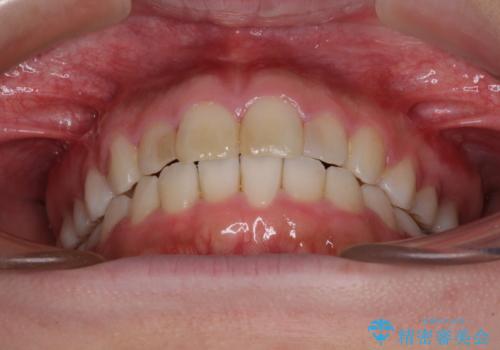

気になる前歯を治したい インビザラインで気づかれずに矯正治療

- ワイヤーではない矯正治療があると聞いたとのことで来院された患者様です。

長年前歯のデコボコを気にしていたもののワイヤー矯正に抵抗があり躊躇していたそうですが、インビザラインなら治療してみたいとのことで相談にいらっしゃいました。

インビザライン適用の歯列であったため、歯と歯の間を削るIPRを用いて改善することとしました。

お仕事柄、長時間のマウスピース装着が苦ではなかったので、歯列はすぐに整いましたが、ゆっくりとした交換頻度であったので、2年ほどの治療期間を要しました。